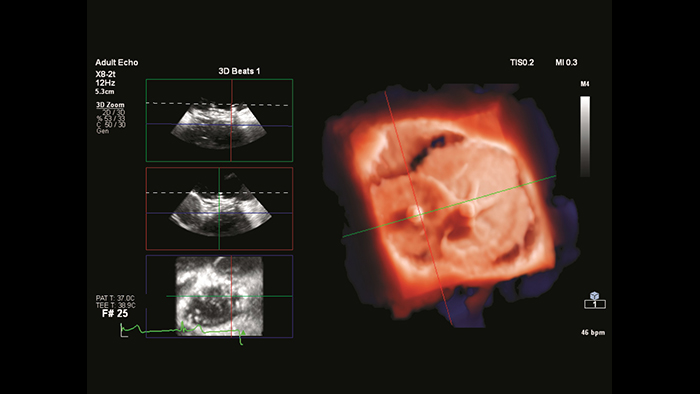

EchoNavigator heart model segmentation